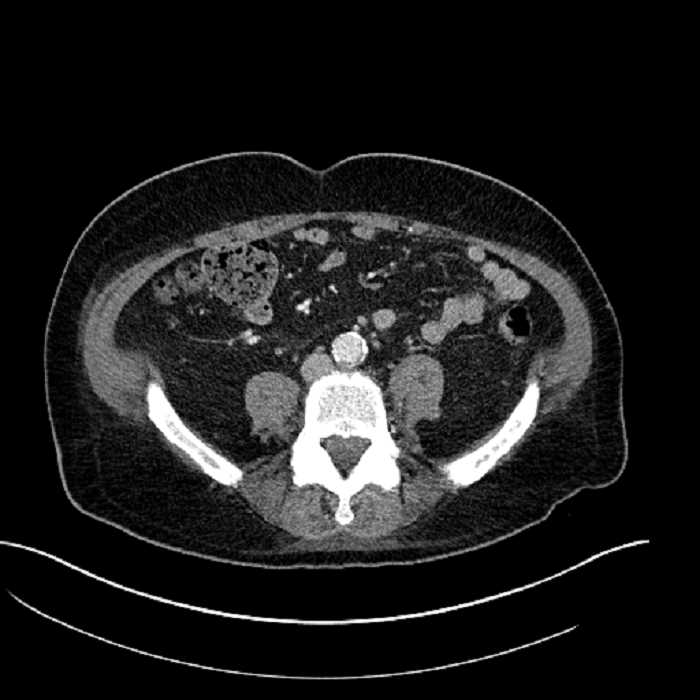

Age: 63

Sex: Male

Indication: Abdominal pain

• Large fluid density structure in hepatic segments 7 and 8 measuring 10 x 7 x 7 cm with internal septation and circumferential ill-defined low density compatible with edema

• Peripherally enhancing subcapsular collections along the anterior margin of the left hepatic lobe measuring 3 x 1 cm and 2 x 1 cm

• Clearly marginated fluid density structure in segment 7 and several other scattered tiny hypodensities, which likely represent cysts

• Mild mural thickening of a segment of the sigmoid colon with adjacent fat stranding and a 1.5 cm fluid and gas collection along the tip of an inflamed diverticulum

• Loss of the normal fat plane between this collection and adjacent loops of small bowel, which demonstrate mural thickening

Acute sigmoid diverticulitis complicated by a small contained perforation and a large abscess in the right hepatic lobe. Additional small subcapsular abscesses along the anterior margin of the left hepatic lobe.

Additionally, loss of the normal fat plane between the peridiverticular collection and adjacent thickened loops of small bowel raises the potential for an enterocolonic fistula.

• The classic CT imaging appearance is a double target sign with internal low density surrounded by an internal enhancing rim (capsule) and a low density external rim (edema)

Hepatic abscess showing the double target sign with low density internally surrounded by a thin inner enhancing rim (red arrow) and ill-defined outer low density rim (yellow arrow). Blue arrow indicates an internal septation. Red arrows: additional smaller subcapsular abscesses. Red arrow: focal contained perforation associated with diverticulitis.